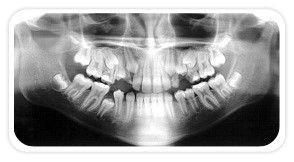

Radiografia mostrando 3º Molares